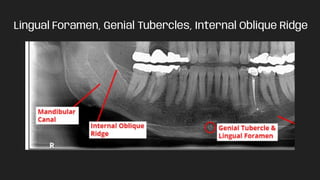

Lingual Foramen, Genial Tubercles, Internal Oblique Ridge

Lingual Foramen, GenialTubercles, Internal Oblique Ridge